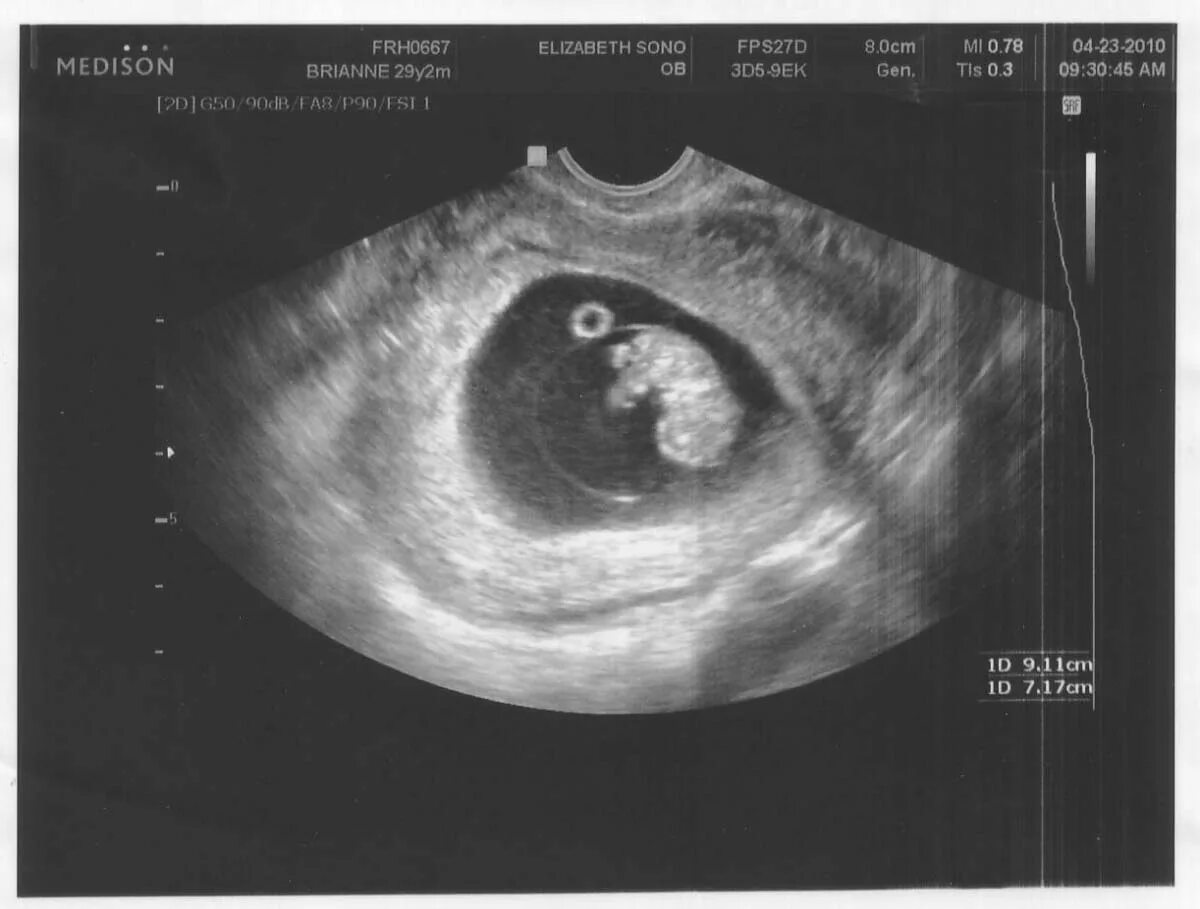

На 4 неделе беременности узи покажет беременность